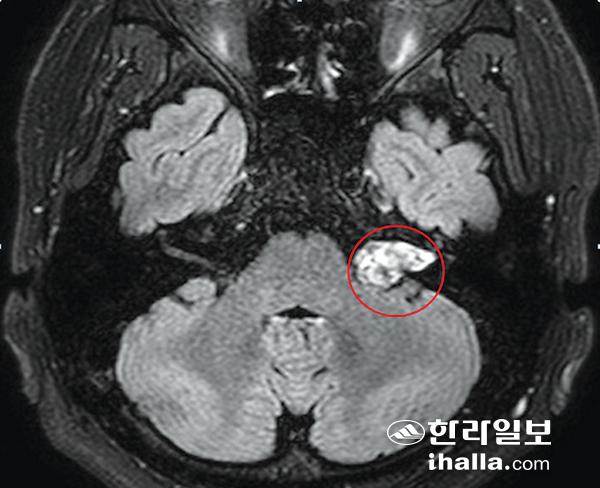

제8번 뇌신경에 발생한 청신경 종양.

60세의 김모씨는 6개월 전부터 오른쪽 귀에 이명이 들렸고 최근 청력이 떨어지는 느낌이 있어 병원을 찾았다가 청신경 종양으로 진단받았다. 양성 종양이라고는 하지만 일종의 뇌종양이 있다고 하니 당황할 수 밖에 없었다. 이명이나 난청, 안면마비 등의 상대적으로 흔한 증상을 이유로 병원을 찾았다가 청신경 종양으로 진단되는 경우가 간혹 있다. 청신경 종양은 제8번 뇌신경에서 생기는 양성의 종양으로 두개 내 종양의 약 8~10% 정도를 차지하며 소뇌교각부에 발생하는 종양의 80~90%에 해당한다. 일종의 뇌종양이지만 잘 관리하고 치료하면 생명에 지장 없이 지낼 수 있다. 9월 9일 '귀의 날'을 맞아 제주대학교병원 이비인후과 송찬일 교수의 도움으로 청신경 종양에 대해 자세히 알아본다.

그러나 약 20% 정도의 환자는 갑자기 귀가 안 들리거나 이명이 발생하는 돌발성 난청을 경험하며, 일부 환자(약 5%)는 청신경 종양이 있음에도 정상적인 청력을 갖고 있다. 또 돌발성 난청으로 진단된 환자의 약 1%에서 청신경 종양이 발견되므로 돌발성 난청 환자는 항상 청신경 종양이 있는지를 의심하고 확인해 볼 필요가 있다. 간혹 어지럼증을 호소하는 환자도 있는데 대개 경도의 평형장애를 보이며 증상이 있는 환자들도 어지럼의 정도가 경미해 어지럼을 신경 쓰지 않는 경우가 많다. 심한 회전성 어지럼을 호소하는 환자는 극히 드물다. 종양이 3㎝이상으로 큰 경우에는 삼차신경을 눌러서 안면감각이 떨어지거나 안면신경을 압박해 안면마비가 발생하기도 한다. 병변이 더욱 진행돼 소뇌나 뇌실을 누르게 되면 보행실조나 뇌압의 증가 소견이 관찰되기도 한다.